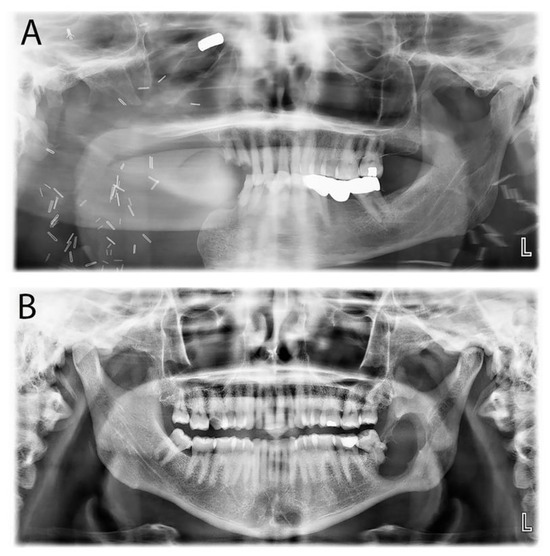

| Primordial odontogenic tumor | POT | Recently described mixed POT exhibiting primitive dental tissue with occasional hard tissue deposition. | Slowly growing lesion in the first two decades and always associated with an unerupted tooth, commonly the third molar. | Well-demarcated, unilocular, bilocular, or multilocular radiolucency associated with an unerupted tooth. |